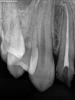

Гость razor Опубликовано 23 мая, 2011 Поделиться Опубликовано 23 мая, 2011 Коллеги, оцените, пожалуйста, снимки. Зуб 1.2.Использовал впервые вертикальную конденсацию, система Beefill, метод непрерывной волны. Беспокоит рентгенконтрастность, по сравнению с термафилом, и вообще, что можно сказать о качестве обтурации? Ссылка на комментарий

Ico Опубликовано 24 мая, 2011 Поделиться Опубликовано 24 мая, 2011 Не плохая вертикалочка))Один совет стараитесь в канале бутылок не делать, шеип должен быть плавныи геиц или ларго в таких каналах ИМХО лишние).http://s013.radikal.ru/i322/1105/cc/4d6e0dedbaae.jpg http://s14.radikal.ru/i187/1105/b3/9ee1dbf4ec62.jpg Как раз в таких местах фрактуры чаще встречаются.А так все Cool)) Ссылка на комментарий